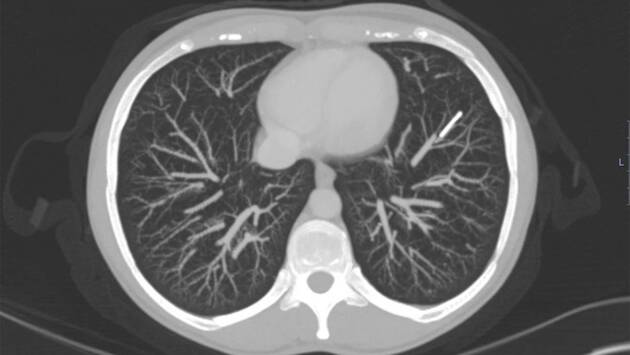

Когда женщина вспомнила про инородное тело в организме, она решила его удалить. Она обратилась к врачам, однако те не смогли обнаружить имплант в положенном месте. В попытках его найти специалисты сначала сделали пациентке рентгенографию, а затем — КТ с контрастом. В итоге имплантат удалось обнаружить в одной из артерий левого легкого, куда он мигрировал по венозному пути через сердце. При этом никаких признаков воспаления в легком, кашля, одышки, боли в груди или кровохаркания у женщины все эти годы не было.

Отмечается, что, если бы она обратилась за медицинской помощью, как только заметила, что не может нащупать контрацептив, его можно было бы извлечь малоинвазивным способом. Однако за шесть лет он врос в легкое, поэтому извлечь его можно было, лишь удалив два сегмента нижней доли органа. Узнав о возможных рисках и осложнениях после операции, женщина от нее отказалась. Поскольку жалоб на здоровье у нее не было, врачи согласились с ее решением, но посоветовали при появлении боли в груди или кашля с кровью незамедлительно обратиться в больницу.